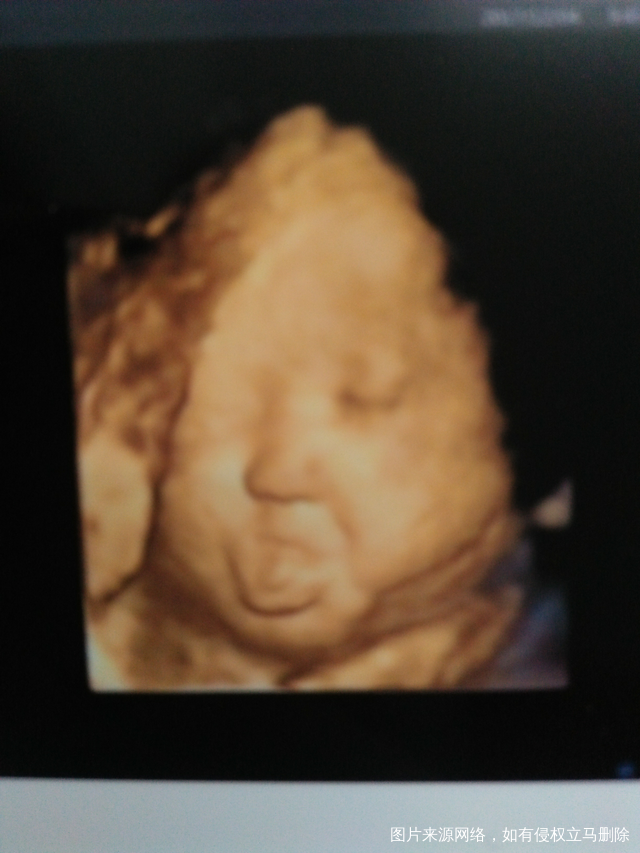

今天照四维,拍到崽崽吐舌头的照片,给姐妹们分享下,虽然其他部位不是很清晰,但我...